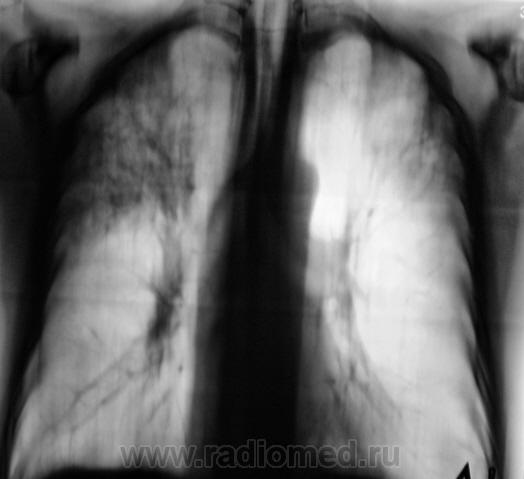

Как всегда, всё началось с "контроля" после флюорографии. Пациента дообследовали согласно стандарту.

Конечно, основная дифференциальная диагностика проводилась между пневмонией и "туберкулёзным поражением".

Но пациент жалоб не предъявляет, клиники - никакой. Коллеги клиницисты - в полной растерянности. Назначили консультацию фтизиатра.

1. Процесс двусторонний.

Архив - 2 года тому флюорография - норма.

Профанамнез - нет, не работал и не жил рядом.

Клиники - никакой, "тухлая", малосимптомная. Мы с коллегой фтизиатром, хотя душа и не лежит, "зрим в корень", как ориентирует В.Б. Серов, и потихоньку, полегоньку меняем вектор на фтизиатрический, а что делать?

Вот, и мы так решили, с учетов ограничеснных возможностей нашей ЦРБ-ушки. Взял коллега фтизиатр "изображения", а также и изображения в динамике, а также необходимый "гарнир", и поехал в головное "фтизное" учреждение. В учреждении проконсультировали и выставили правосторонний инфильтративный. Ну и у нас считай - гора с плеч...

Людмила Григолрьевна, но тут, то процесс двусторонний, хоть преимущественно правосторонний. А на полноформатных изображениях (томограммах), и очаги справа в среднем и нижнем легочных полях дифференцировались.